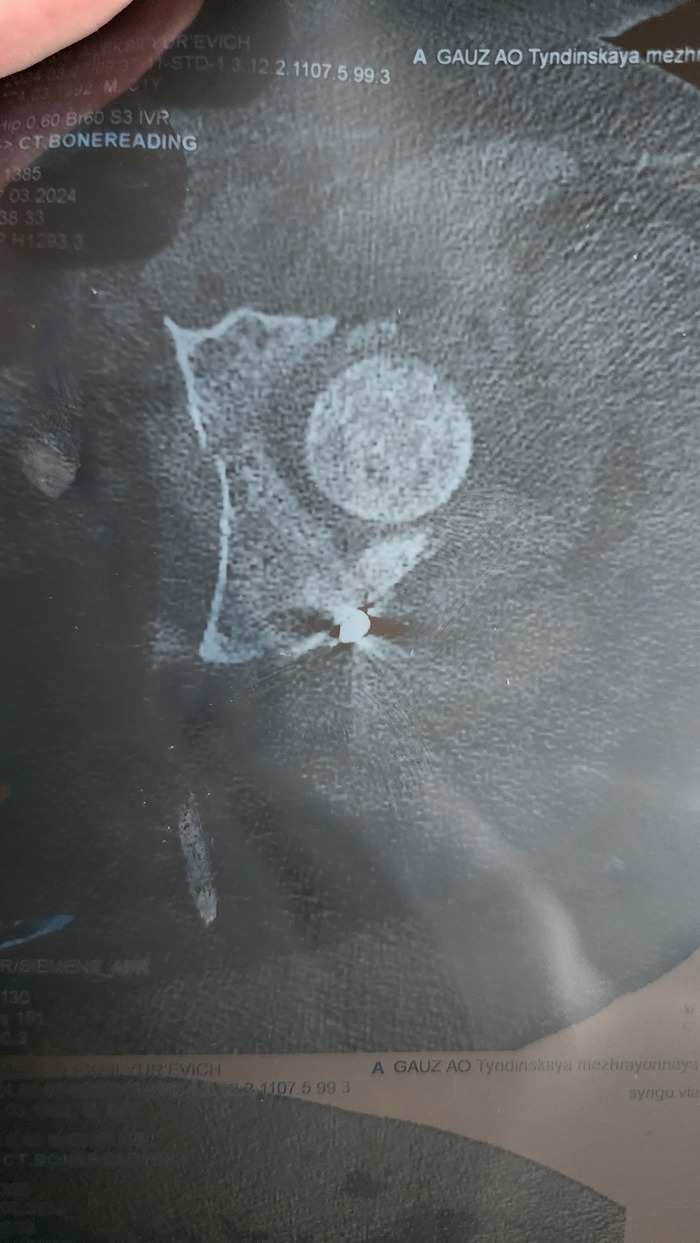

Всем привет, и так, моя эпопея с этим переломом наконец то кончилась, скажу сразу что все таки пришлось менять таазобедренный сустав. И так начнём все попорядку....... После продолжительных попыток хоть как то сохранить свой сустав, пришёл к выводу что это все как мёртвом припарка и начал искать себе врача и клинику, где мне бы могли его грамотно заменить. Очень много слышал от врачей что походи ещё немного, всегда успеешь его заменить, ты ещё молодой, и т.д и т.п, но самый веский аргумент в мою пользу был то что я попросту не мог нормально ходить, были дикие боли, прострелы и прочее, которые меня неустраивали от слова совсем, да и на работу с такой ногой я тоже не как не мог пойти(элементарно, не мог пройти комиссию). Предлагали множество вариантов по лечению асептического ннкроза типо тунелизации и прочих операций, которые в моем случаи представляли сомнительный результат и в итоге все равно приводили бы к протезированию! Так вот, нашёл я врача в городе Барнаул, там целый федеральный центр протезирования. Сначала позвонил туда и записался на приём по видеосвязи, где посмотрев предварительно мои снимки и результаты мрт решили менять сустав и не тянуть время. И вот ровно через год и один месяц после ДТП 22.01.2025 я поменял тазобедренный сустав. После операции я если честно просто охринел, меня подняли с кровати на следующий день и сказали пройтись по коридору на костылях, что у меня получилось просто великолепно( на большое удивление мне, ведь после первой операции я не мог встать около недели). Больница просто огонь, все добрые, ухаживают, присматривают! Ну и по итогу всего рассказа, сейчас прошло уже 9 месяцев, и я практически восстановился до того момента как было до ДТП. Есть конечно небольшой дискомфорт иногда, ну я думаю что это все терпимо. Вот так прошли мои 2 года после этой аварии. Люди будте внимательней на дорогах, не будет мудаками, очень хреновые вещи происходят когда машины врезаются, и очень неприятно когда в такие ситуации попадают люди не по своей вине, а ушлепки которые вылетают на встречку, остаются безнаказаными и сука более менее целыми!